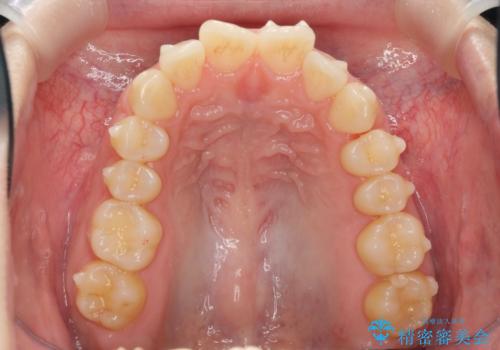

マウスピース 狭窄歯列の改善

- 噛み合わせが深い、笑った時の歯並びの改善を求めて来院されました。

マウスピース型の矯正装置インビザラインを用いた治療を計画します。

狭くなってしまった歯並びを放物線状に並べることで噛み合わせの安定・見た目の改善・ガタつきの改善を達成することができました。